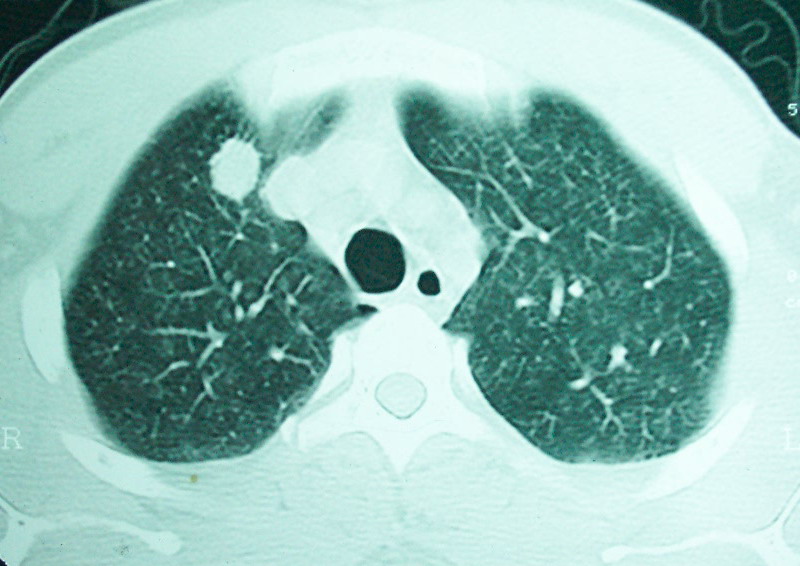

我看是不是可以两元化来解释,左肺下叶还是肺脓疡,而其余病灶考虑肺癌伴肺内转移,我看右肺上叶尖段病灶可见明显毛刺改变为原发病灶.

1、左下肺鳞癌伴两肺及纵隔淋巴结转移;

2、两上肺支扩伴慢性炎症。